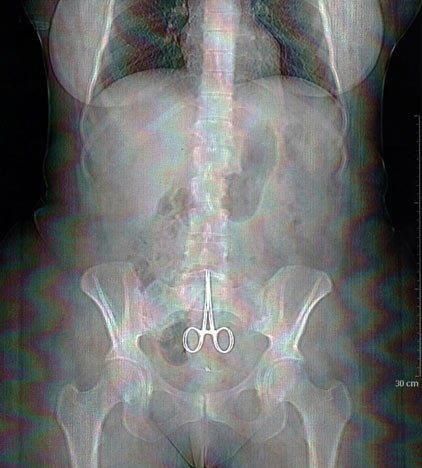

A x-ray made on February 13, 2011 in Lyon, shows a pair of surgical pliers in the abdomen of Anne, a women who complained of abdominal pain after a surgery. Six months after her surgical operation, Anne realized she had a pair of surgical pliers which had been forgotten in her womb, when the point of the pliers pierced her navel following a "good fit of coughing" on last february 11